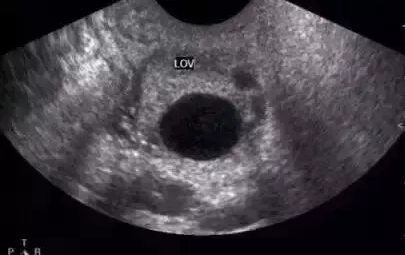

正常成熟的優勢卵泡的聲像圖

① 卵泡最大直徑達20mm,優勢卵泡最大直徑范圍為17~24mm,體積2.5~8.5mm³。徑小于17mm者為非成熟卵泡。

?、?卵泡外形飽滿呈圓形或橢圓形,內壁薄而清晰,或可見內壁卵丘所形成的一金字塔形的高回聲,多在排卵前24~30小時易于顯示。亦可見優勢卵泡周圍有一低回聲暈(多由排卵前卵泡膜組織水腫所致)。

?、?卵泡位置移向卵巢表面,且一側無卵巢組織覆蓋,并向外突出。

卵泡的聲像表現為圓形或橢圓形無回聲區,位于卵巢皮質內,邊界清晰,囊壁菲薄,內壁光滑。在月經的早期,卵巢皮質內可見多個直徑3~5mm的小卵泡,隨著月經周期的推移,卵泡逐漸增大,形成優勢卵泡,而其它小卵泡逐漸萎縮。主導卵泡成熟,逐漸突出于卵巢表面。對卵泡的觀察除注意其形態、數目、回聲外,測量卵泡的大小對了解其生長發育狀態、藥物治療效果以及判斷卵泡成熟是十分重要的。

成熟卵泡的特點

?、?卵泡最大直徑超過20mm,排卵前正常卵泡最大直徑范圍為17~24mm。

?、?卵泡外形飽滿呈圓形或橢圓形,內壁薄而清晰。

?、?卵泡位置移向卵巢表面,且一側無卵巢組織覆蓋,并向外突出。如果在測卵泡的時候出現卵丘,即意味著即將排卵(卵丘的出現率卵泡內一側內壁上可見細小高回聲點,即為卵丘)。